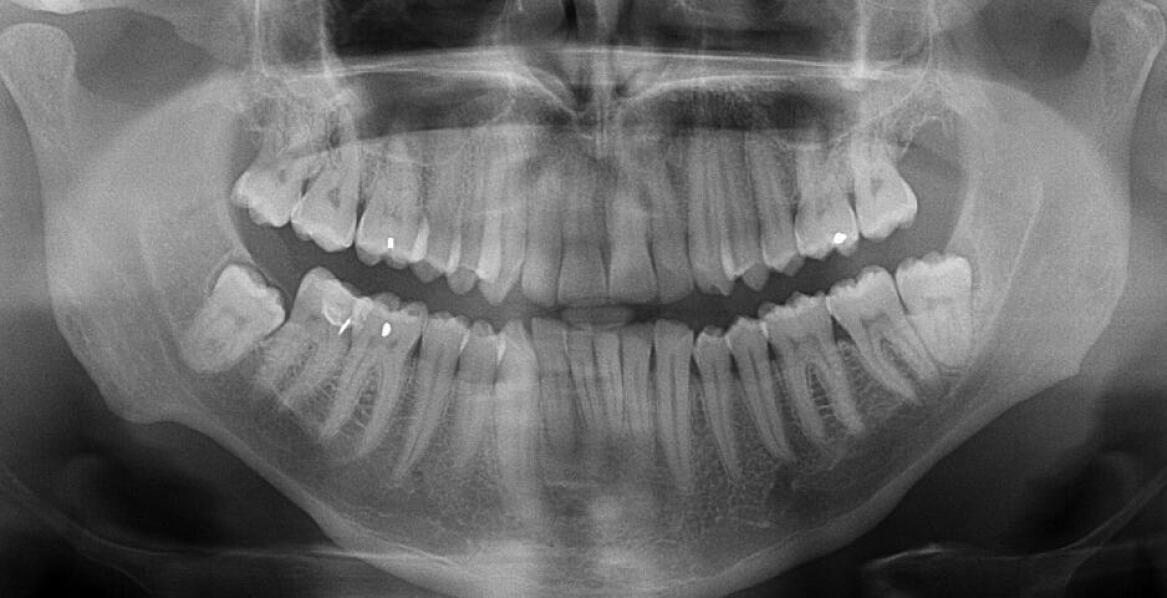

Jak radiowizjografia wspiera diagnostykę w stomatologii estetycznej?

Nowoczesne podejście do diagnostyki w stomatologii estetycznej opiera się na radiowizjografii, która rewolucjonizuje sposób obrazowania zębów oraz struktur otaczających. Dzięki tej technice lekarze uzyskują wyraźne i szczegółowe obrazy, co pozwala na dokładniejszą ocenę stanu uzębienia. W artykule o